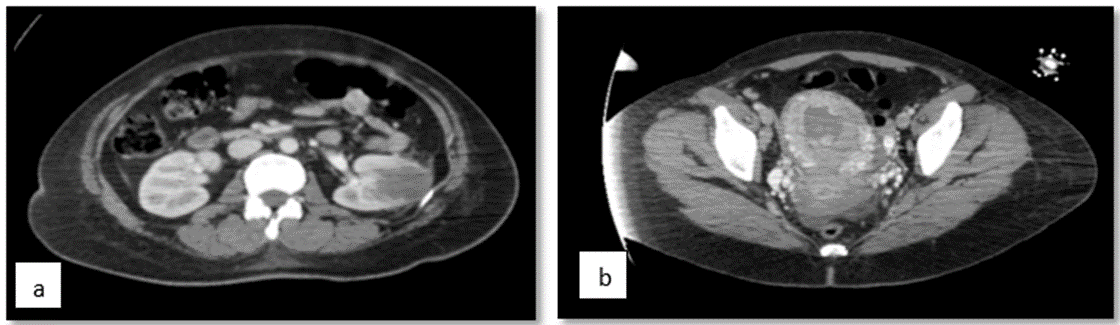

Given these findings, an extension of the search for lesions was carried out, finding in neck tomography, numerous lymph nodes in the different spaces of the neck, the largest of which was projected in left station III with a diameter of 12 mm in the short axis. And in the bone system with the presence of a small lytic image projected on the vertebral body of C5. In tomography of the abdomen and pelvis (Figure 4), in the middle third of the left kidney the ill-defined hypodense image of 34 × 33 mm with soft tissue density, central uterus with thick endometrium of 31 mm of heterogeneous content. With the rest of the tumor markers reported (Table 3).

occrs-molar

Figure 4. Abdominopelvic tomography which shows in the middle third of the left kidney the ill-defined hypodense image of 34 × 33 mm with soft tissue density, central uterus with thick endometrium of 31 mm of heterogeneous content.